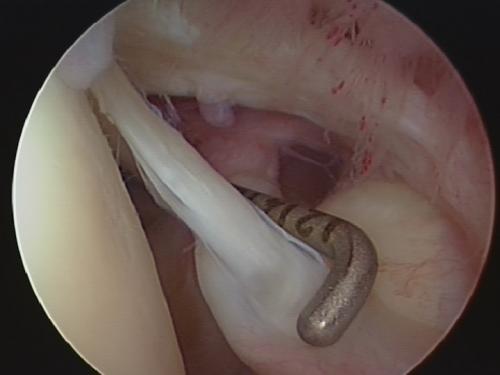

Операция выполняется под общей анестезией артроскопически. Это значит, что через один разрез кожи длиной около 1см в полость сустава будет введена

Затем производится осмотр всех важных структур и оценка их состояния. К этим структурам относятся хрящ суставных поверхностей, сухожилия капсулы сустава и вращательной манжеты. Важные находки могут быть зафиксированы в виде цифровой фотографии или видео HD-качества.

Иллюстрация: эндоскопия плечевого сустава

Поврежденные структуры восстанавливаются с использованием наиболее современных методик. К повреждениям, которые можно восстановить артроскопически, относятся: нестабильность, повреждения длинной головки двуглавой мышцы, адгезивный капсулит. Вторая часть операции производится в пространстве над головкой плечевой кости – в подакромиальном пространстве. Здесь находится причина хронического бурсита и повреждений сухожилий вращательной манжеты. После обработки хронического бурсита взгляду хирурга открываются многие важные элементы плечевого сустава. Дефекты сухожилий вращательной манжеты могут быть восстановлены при помощи швов и якорных фиксаторов. Кальцификат при кальцифицирующем тендините обнажается после обработки хронического бурсита и может быть легко удалён. Последним осматривается акромиально-ключичный сустав, артроз которого может причинять значительную боль при обычных бытовых нагрузках.